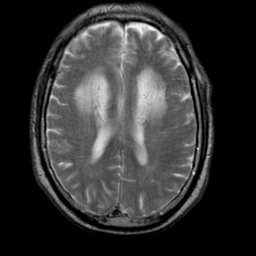

Meningioma, MR Study #2 -- Slice #12

[Home][Help][Clinical] Slice 12